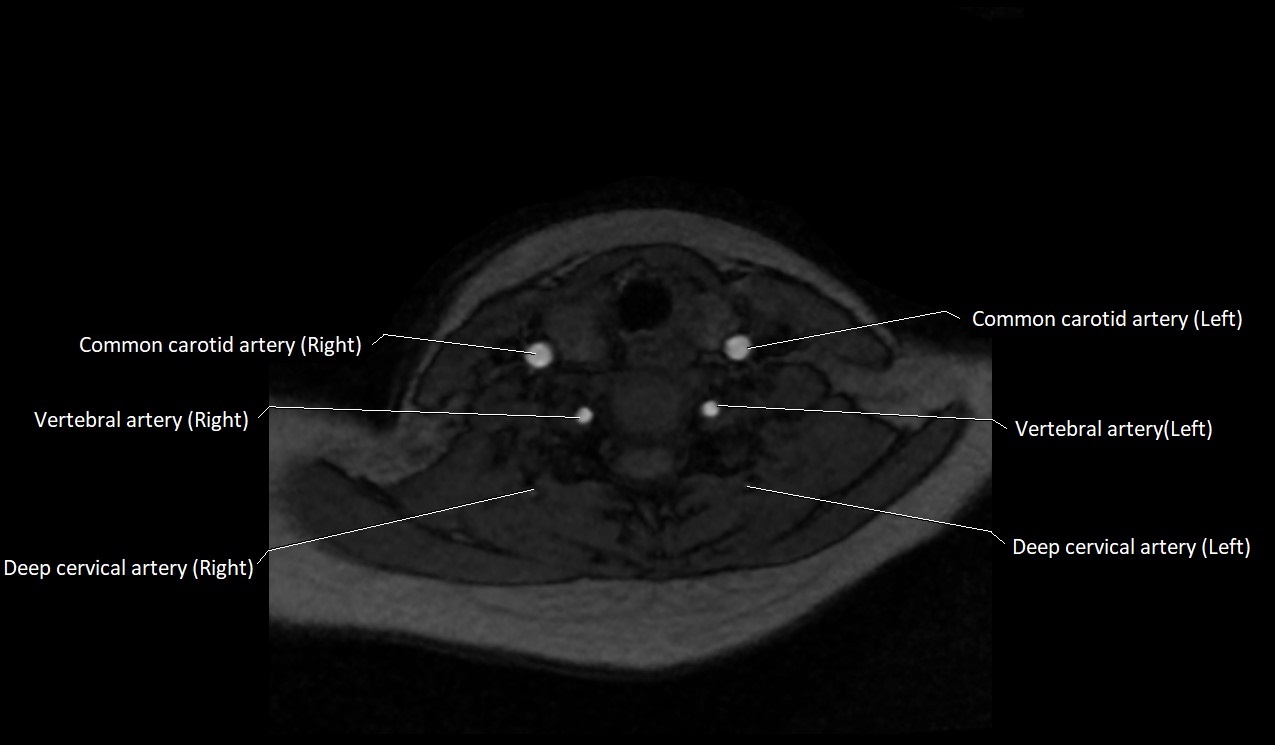

MRI images

image